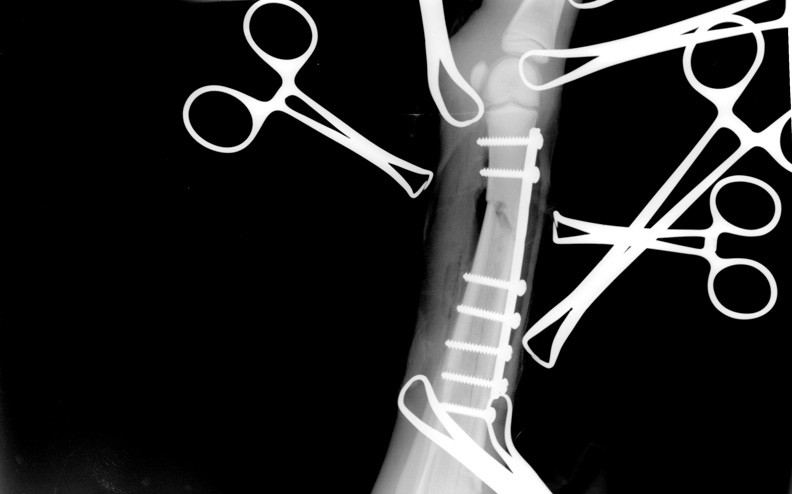

2. Odpowiednie zabezpieczenie złamania. Podwieszenie źrebaka na czas transportu.

Właściciel instruowany przez lekarza weterynarii wykonał je samodzielnie. Złamanie kości podudzia.

- Złamania – Na szczęście żyjemy w czasach, w których leczenie wielu złamań może zakończyć się powodzeniem i nie jest już bezwzględnym wyrokiem śmierci dla zwierzęcia. Na powodzenie leczenia nakłada się wiele czynników między innymi: szybkość reakcji, odpowiednie zabezpieczenie w czasie transportu, dobrze dobrana terapia przeciwbólowa (należy uspokoić zwierzę, jednak całkowite zniesienie bólu niesie ze sobą ryzyko, iż koń zacznie stawać na złamanej kończynie co znacząco pogorszy sytuację), przebieg operacji i powodzenie znieczulenia, kluczowy moment – wybudzania i wstawania konia (niestety pod wpływem ciężaru ciała lub paniki konia podjęte przez chirurga próby zespolenia kości mogą ulec zniszczeniu), opieka pooperacyjna. Podsumowując złamanie to kolejna sytuacja, w której liczy się czas. Im szybciej złamanie zostanie zabezpieczone i koń znajdzie się w klinice, tym większe są szanse na jego uratowanie. O przebiegu naszych działań i ryzyku samego transportu musi poinformować lekarz weterynarii.